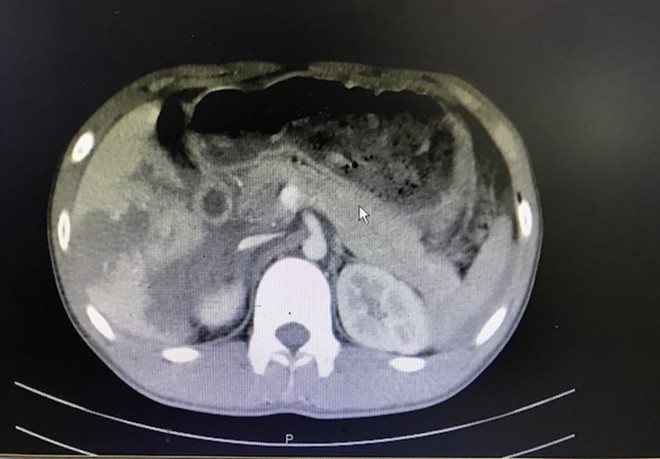

Tại đây sau khi siêu âm, các BS chẩn đoán bệnh nhân bị đa chấn thương, có dịch ổ bụng lượng nhiều. Bệnh nhân tiếp tục được xử trí giảm đau và bù dịch, đồng thời được chỉ định chụp CT scanner toàn thân. Kết quả chụp CT toàn thân cho thấy, bệnh nhân vỡ gan phải độ III-IV, dập tá tràng và đầu tụy, tụ máu sau phúc mạc gây xuất huyết ổ bụng, tràn khí màng phổi 2 bên, gãy xương sườn 2 bên, gãy xương đùi phải. Đây là tình trạng chấn thương nguy kịch, sốc mất máu và có thể mất mạng bất kỳ lúc nào.